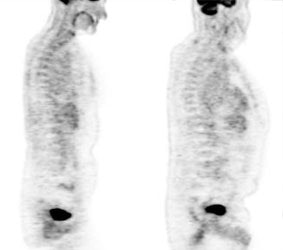

Metformin bowel activity: A large

amount of bowel activity can be seen in this patient

that was taking metformin. |

|

|